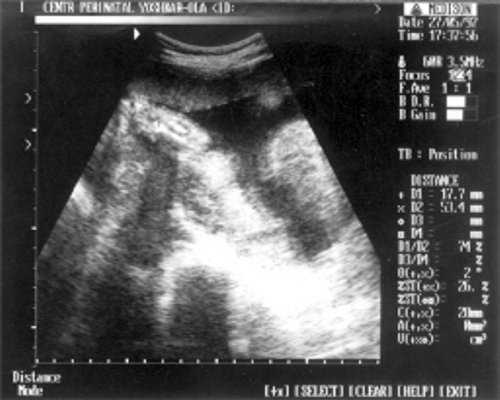

- Плечевая кость = 16 мм - 14,5 нед. (рис. 3)

Рис. 3. УЗИ плода - плечевая кость.